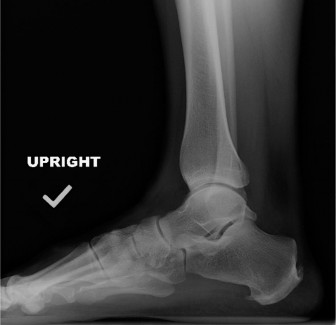

A 57-year-old female presents with an 8-month history of pain at the Achilles tendon insertion. She reports a…